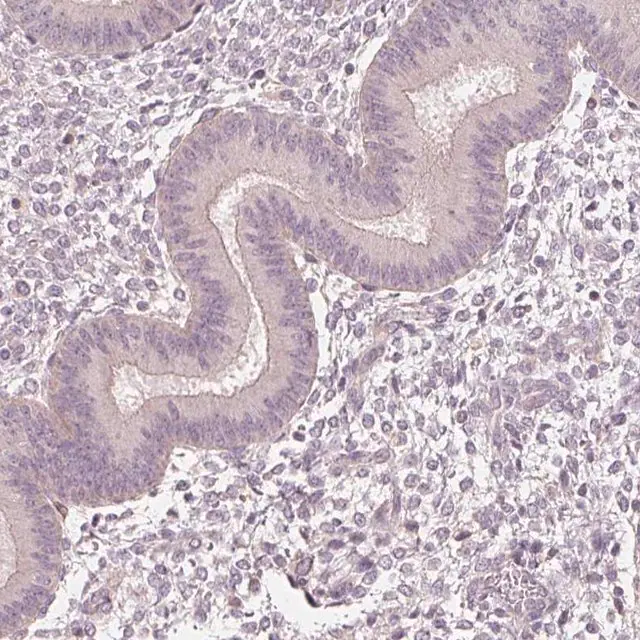

| General description【一般描述】 | Aquaporin 8 (AQP8) belongs to the water channel proteins, aquaporins (AQPs). The protein is expressed in human pancreas and colon. It encodes a 261 amino acid protein. The gene is located on human chromosome 16p12.1. |

| technique(s) | immunohistochemistry: 1:500- 1:1000 |